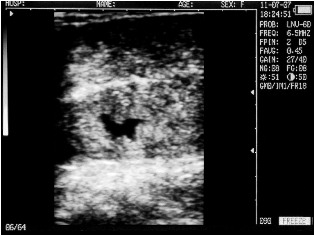

Cow with calf. Deadline - 25 days